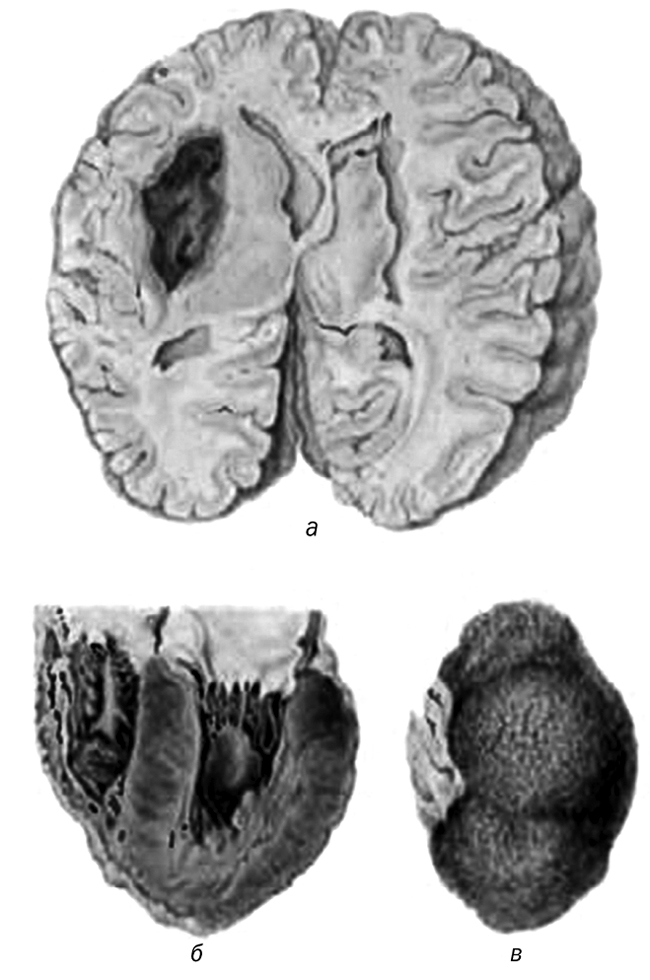

Обычно она связана с разрывом гиалинизированного сосуда и развитием массивного кровоизлияния в мозг (геморрагический инсульт) по типу гематомы (рис. 7, а). Прорыв крови в желудочки мозга всегда заканчивается смертью больного.

Рис. 7. Гипертоническая болезнь:

а – кровоизлияние в левом полушарии головного мозга; б – гипертрофия миокарда левого желудочка сердца; в – первично-сморщенная почка (артериолосклеротический нефросклероз)

Почечная форма. При хроническом течении гипертонической болезни развивается артериолосклеротический нефросклероз (рис. 8), связанный с гиалинозом приносящих артериол. Уменьшение притока крови приводит к атрофии и гиалинозу соответствующих клубочков. Их функцию выполняют сохранившиеся клубочки, которые подвергаются гипертрофии.

Поэтому поверхность почек приобретает зернистый вид: гиалинизированные клубочки и атрофированные, склерозированные нефроны западают, а гипертрофированные клубочки выступают над поверхностью почек (рис. 7, в; рис. 8). Постепенно склеротические процессы начинают преобладать, и развиваются первично-сморщенные почки. При этом нарастает хроническая почечная недостаточность, которая